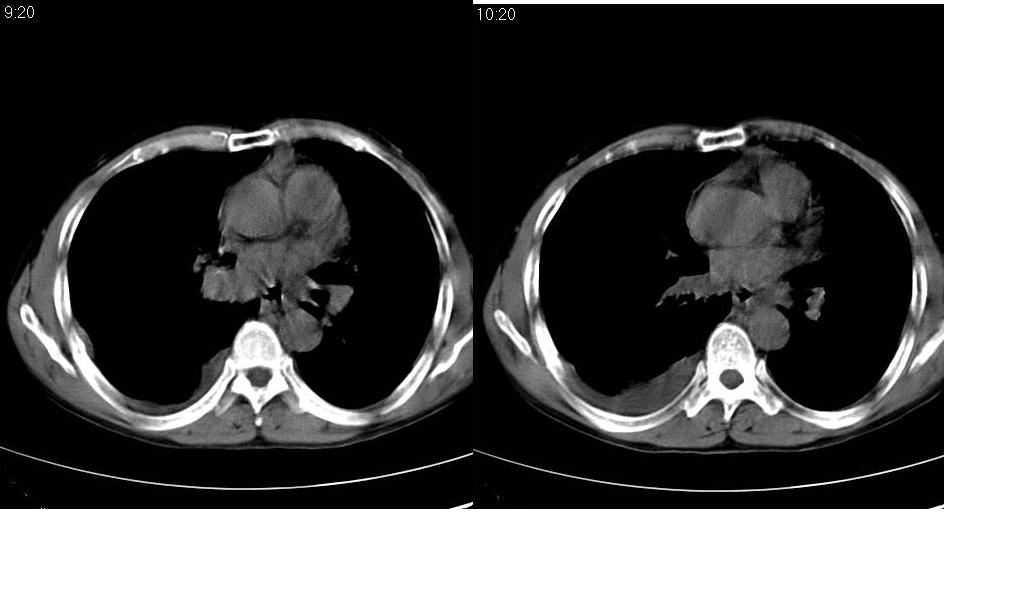

考虑:1、右肺下叶中心型肺癌并纵隔淋巴结转移。胸腔积液。

2、心包少量积液。

3、左肺改变不除外癌性淋巴管炎或化疗后肺间质纤维化。

纵隔及右肺门淋巴结肿转移,右肺改变是否为阻塞性肺气肿改变?左肺改变支持淋巴管炎的诊断;化疗后肺改变应该双肺都有改变。

考虑:1、右肺下叶中心型肺癌并纵隔及左肺门淋巴结转移。胸腔积液。

3、左肺改变与左肺门肿大淋巴结影压迫主支气管有关。